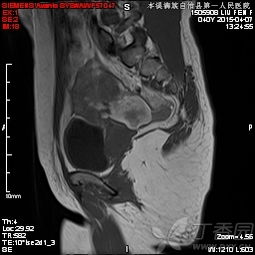

6、盆腔內(nèi)病變:包括膀胱、前列腺、子宮、卵巢、直腸良、惡性占位病變,特別是前列腺增生,子宮內(nèi)膜異位癥等。MRI多方位、大視野成像可清晰地顯示盆腔的解剖結(jié)構(gòu)。尤其對(duì)女性盆腔疾病具有重要診斷價(jià)值,對(duì)盆腔內(nèi)血管及淋巴結(jié)的鑒別較容易,是盆腔腫瘤、炎癥、子宮內(nèi)膜異位癥、轉(zhuǎn)移癌等病變的最佳影像學(xué)檢查手段。